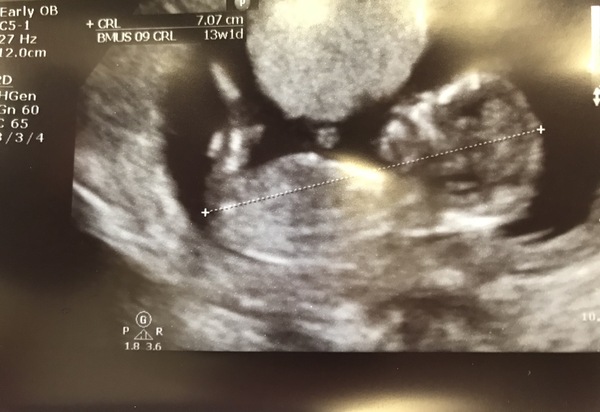

So im 13+1 and ive got my ‘second’ scan today at 10am, had my 12 week one last week but baby was doing hand stands and not in the correct position to measure so fingers crossed baby plays ball today! Saying that i hope the snow holds off and doesnt come PITA.

Scan all done! Everything went well, took the Nuchal measurement which was 1.5mm so that was good. Just got to see if i hear anyting back from the bloods.